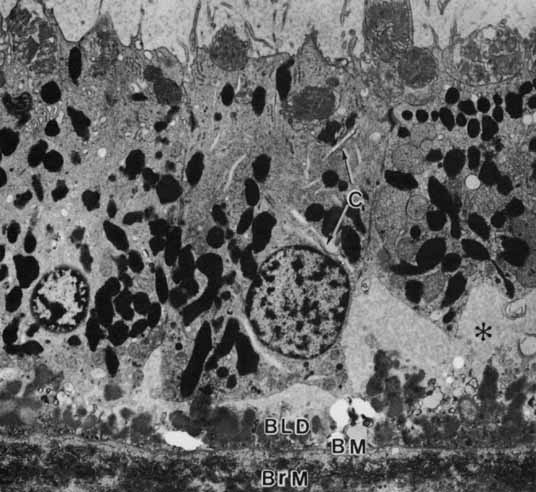

Age-related macular degeneration (AMD) is the leading cause of blindness among adults. Although the specific causes of AMD remain unknown, these include a combination of intrinsic (i.e., genetic predisposition) and extrinsic (i.e., environmental insult such as toxic and/or photooxidative damage) factors that have their primary impact on the RPE.71 AMD is associated in its early phases with the buildup of incompletely metabolized waste products in association with the RPE, both intracellularly (i.e., lipofuchsin) (Fig. 17) and extracellularly (i.e., drusen) (Figs. 18 and 19). Subsequent malfunction of the RPE proper, and/or Bruch's membrane, lead to the progression of AMD from its “dry” state with damage to the RPE and neural retina, wherein the focus of the lesion remains at the RPE/neural retina interface, to the “wet” state wherein signals that possibly originate with the RPE result in abnormal responses in surrounding tissues resulting in neovascularization in the choriocapillaris.72 Evidence to support the “toxic accumulation” hypothesis has come from studies of Stargardt's disease, a form of juvenile macular degeneration, whereby a primary defect of lipid metabolism in the neural retina leads to accumulation of toxic products following their uptake by the RPE, whose failure then subsequently leads to photoreceptor loss.73

Fig. 19 Macular retinal pigment epithelium of a 97-year-old woman showing the basal linear deposit (BLD) internal to the basement membrane (BM). The retinal pigment epithelium has no basal infoldings and no apparent attachment foci to anchor the cells to Bruch's membrane. Clefts (C) in the cytoplasm may be elements of the Golgi apparatus. The asterisk marks subretinal pigment epithelial proteinaceous fluid (Ph, phagosome; ×4,600).